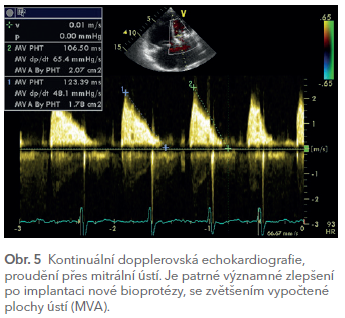

Výkon proběhl 21. ledna 2021 na II. interní klinice VFN v Praze bez komplikací a měl výrazný efekt na subjektivní obtíže nemocné, ústup srdečního selhávání a v echokardiografickém obraze na zlepšení proudění přes mitrální ústí (MVA 1,8–2,1 cm2, jen zcela stopová regurgitace na protéze, zmenšení velikosti levé síně, snížení plicní hypertenze) (obr. 5). Pacientku jsme po mnoha týdnech léčení mohli propustit do ambulantní kardiologické péče.